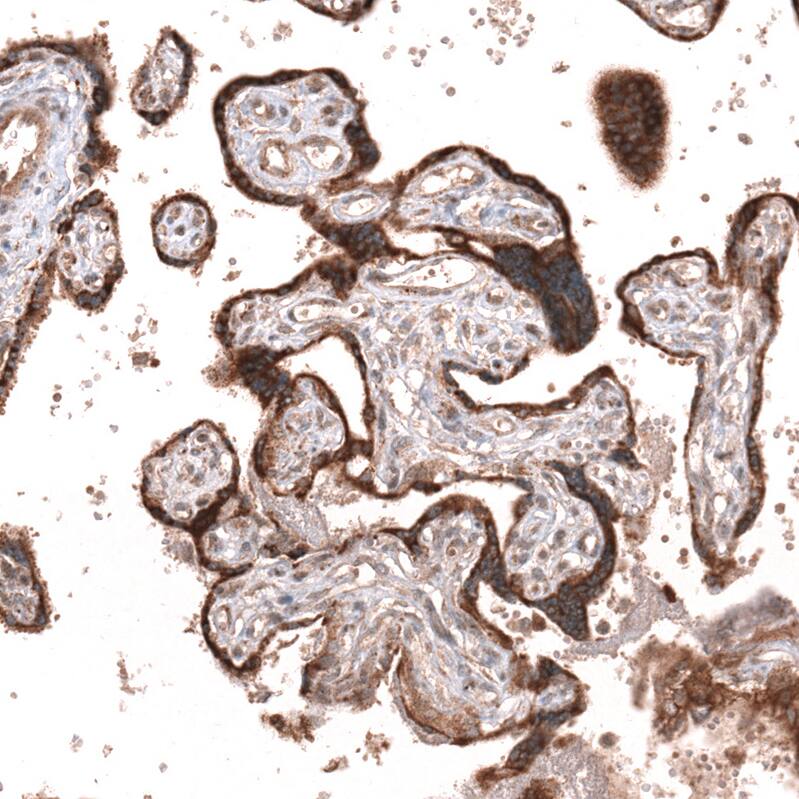

Staining of human fallopian tube shows moderate cytoplasmic positivity in glandular cells.Immunohistochemistry-Paraffin: Wnt-5a Antibody [NBP3-43867]

Staining of human placenta shows strong cytoplasmic positivity in trophoblastic cells.Applications for Wnt-5a Antibody (CL13683) - Azide and BSA Free